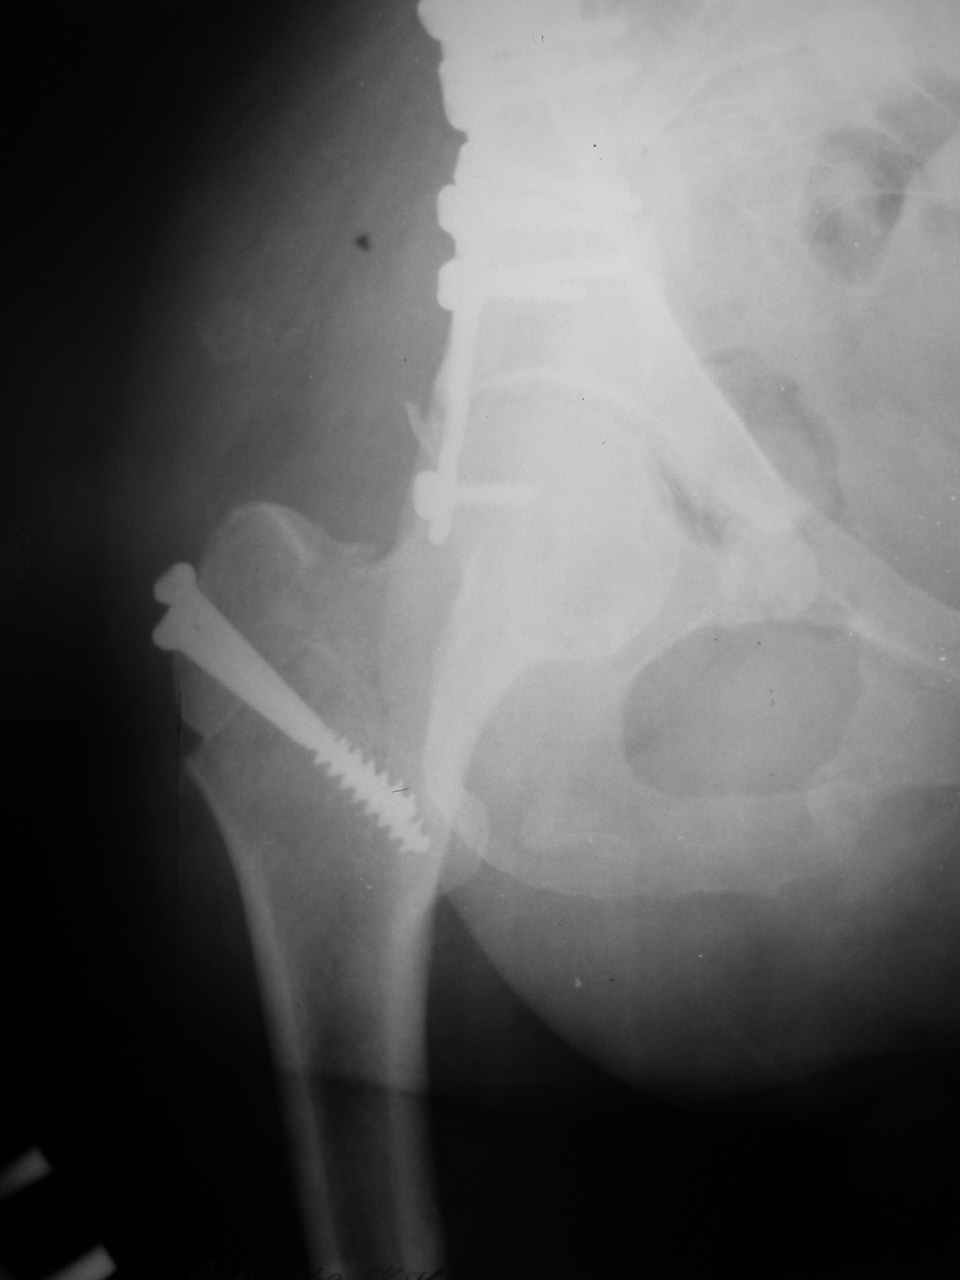

А какой отдел вертлужной впадины более важен передний или задний? Чем был обусловлен выбор доступа к суставу? Проще говоря, почему вы пошли передним доступом на двухколонный перелом? Мне понятны ваши сомнения, когда не удется сделать все что хотелось бы. В данном случае доступ должен быть чрезвертельным боковым (как и советовал Рунков) или двумя доступами.

Сложностью, ассоциативностью характера перелома, я бы с радостью воспользовался мининвазивной перкутанной фиксацией винтами, но боюсь, что результат был бы ещё хуже, техникой непрямой репозиции перелома не владею, поэтому пытаясь получить анатомичную впадину приходится широко открывать, по крайней мере пока, а дальше буду пытаться уменьшать пространство...

> передним доступом на двухколонный перелом?

Илеофеморальный доступ не совсем передний и сравнительно с илеоингвинальным, и Кохера-Лангенбека открывает весь наружный таз кроме самых передних отделов лонных костей, фиксацию которых я не ставил в задачу. Обширность диссекции, большая длительность операции и более высокий риск гетерооссификации - отрицательные моменты в обмен на возможность легче ориентироваться.

Вопрос доступа к вертлужной впадине при остеосинтезе задача не простая. Конечно, у Летурнеля и Тайла всё давно описано, нам остается только брать на вооружение. Но сами понимаете, что не бывает двух одинаковых ситуаций, поэтому в каждом случае вопрос решается сугубо индивидуально. Наша главная цель - восстановить анатомию с нанесением минимальной дополнительной травмы тазобедреннному суставу, думаю с этим никто не поспорит. Расширенный илиофеморальный доступ уж слишком травматичен (как сказал один коллега "таз лежит отдельно, больной отдельно").Стоит ли делать из пациента анатомический препарат для того чтобы легче ориентироваться. Да и нужно ли собирать всю "мозаику"? Мы применяли при таких операциях своеобразную операционную хитрость - сначала устраняли грубое смещение крыла под гребнем с фиксацией так называемой "плавающей" пластиной (временно фиксированной на двух винтах)- доступ или продлевали боковой, или делали небольшой дополнительный разрез над гребнем. Это позволяло устранить грубое смещение и захождение отломков тела повздошной кости, что значительно облегчало репозицию и остеосинтез впадины над сводом. Основное внимание конечно же уделяли нагружаемому задне-верхнему отделу. Сообщите ваш адрес, пришлю схемы и рентгенограммы.